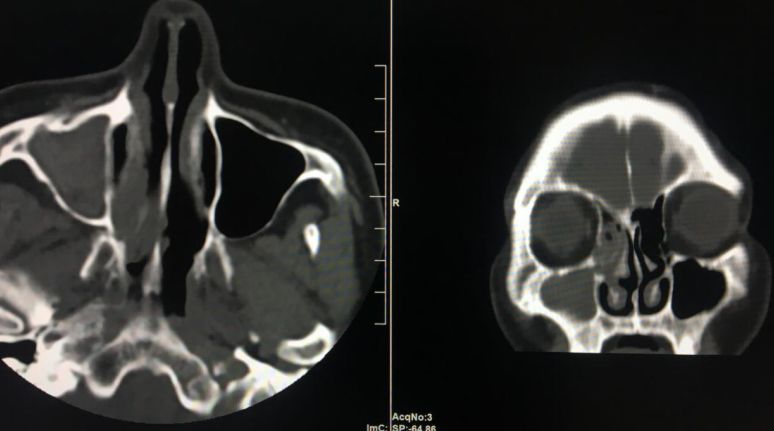

全新日本进口佳能金刚螺旋CT

该新设备功能先进,有平扫、三维重建、X线计算机体层成像等功能,能对人的头部、颈部、胸腔、四肢、盆腔等多个部位进行扫描成像。

现在医院引进了全新的进口螺旋CT,患者直接就能在医院确诊,节约了患者的时间,并且,进口的螺旋CT机扫描图像质量好,显示清晰。

右侧上颌窦炎

该设备自运行以来,发现并确诊不少疾病:颈椎椎间盘突出、 腰椎椎间盘膨出伴双侧神经根受压、硬膜外血肿、右侧上颌窦炎、右侧筛窦炎、双肺感染伴双侧胸腔积液、心包积液、右侧胸腔包裹性积液、原发性肝癌伴骨转移等疾病。